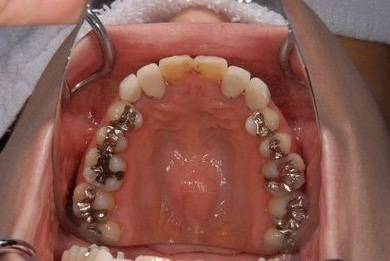

治療内容 オールセラミッククラウン2本(オールセラミック用の土台2本)

治療部位

1 1

治療前

• 治療前